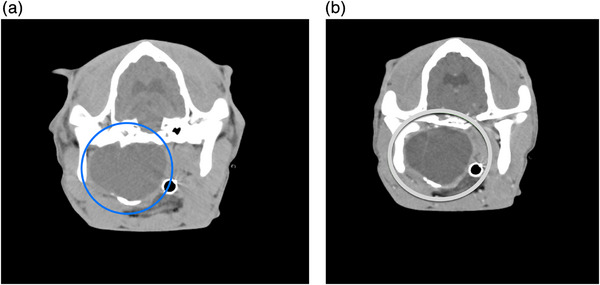

A 6-month-old, intact female Boxer presented with ongoing dyspnea, nasal congestion, cardiac arrhythmias, stertor, and syncope. A CT assessment of the head, neck, thorax, and abdomen revealed a fluid to soft tissue attenuating mass with an incomplete mineralized rim centered on the soft tissue ventral to the right tympanic bulla. Histopathologically, epithelialization was consistent with a dermoid cyst. The severe degree of mass effect caused by this abnormally and undocumented ossified structure in vital cranial cervical organs causes more systemic complications than traditional dermoid cysts. CT delineated the cyst's structure and compression/occlusion of adjacent structures.